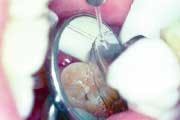

Because the failure rate among sealants is so high, we meticulously examine each sealant our patients have. The examination includes placing a caries-detection dye on the sealants using high resolution video-imaging. If a sealant is leaking, good magnification will show the tint of the dye under the sealant. A failed sealant is then easily removed, utilizing the parallel water stream technique. The operative field is flooded with water, while air abrasion is simultaneously used to selectively remove the sealant.